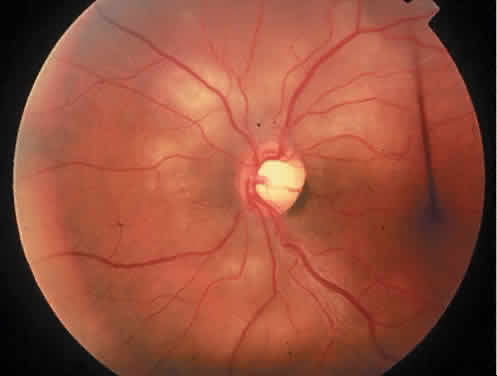

The term hyperhomocysteinemia describes a variety of disorders that cause elevated plasma levels of homocysteine, homocystine, and their metabolites. Homocysteine is an amino acid formed during the metabolism of methionine. Vitamins B12 and B6 and folate serve as cofactors in the metabolism of methionine (Fig. 4).